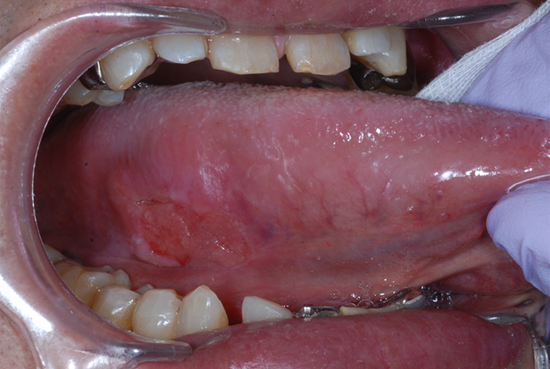

舌癌について

舌癌ってどんなものかしってますか? 舌がんとは口の中にできたがんのことを、総じて口腔がんといいますが、舌がんとは一般的に、舌の前方2/3(口を大きく開けたときに見える範囲)に生じたがんのことを指します。 口腔がんの中では […]